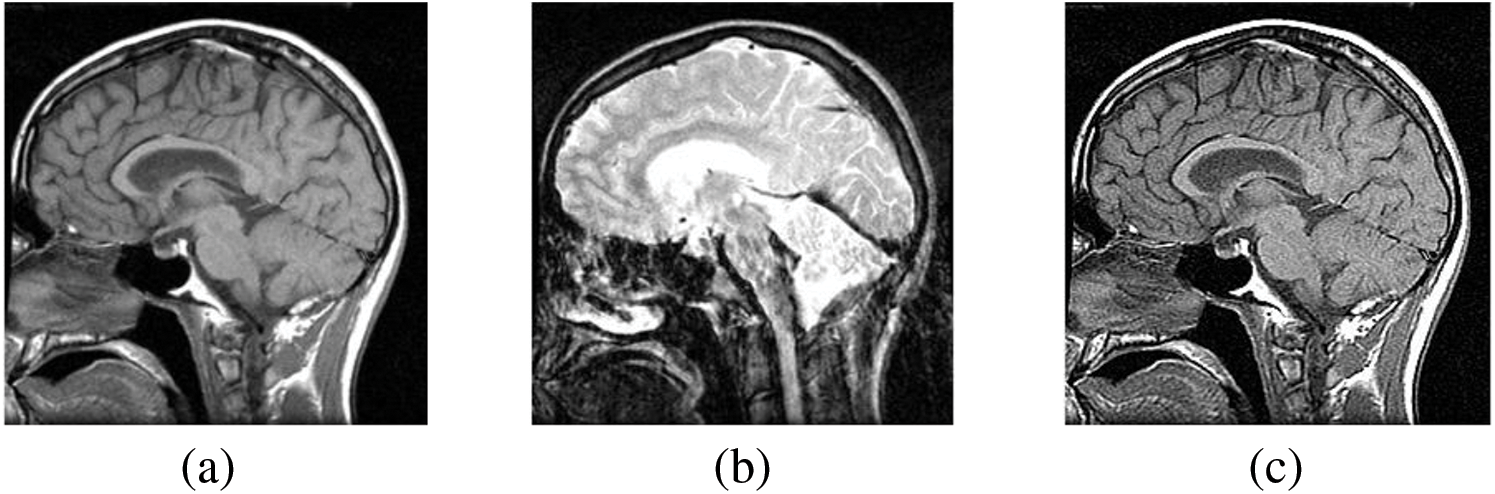

Figs. 4–11 display the original CT and MRI images along with their corresponding enhanced images obtained through the proposed sharpening technique, including Unsharp masking and LF+DFT Sharpen. The enhanced images effectively highlight and enhance minor details, making them clearer and more perceptible. These enhanced images play a crucial role in subsequent stages of the fusion process, where the aim is to integrate the essential information from both CT and MRI modalities.

Figure 7: The sharpened results of “Brain CT and MRI Image set 2” (a), (b) are two source images CT and MRI, respectively, (c), (d) are sharpen images by Unsharp masking and (e), (f) LF+DFT sharpened images

Figs. 4–11 present the fused images obtained from both existing and proposed hybrid approaches. The existing approaches, including PCA, MF, DWT, DTCWT, DCHWT and SWT, initially fuse the source images. Then, the SWT method is combined with the proposed sharpening techniques and applied to fuse the sharpened images. Comparatively, the fused images generated by the proposed methods, namely SWT+Unsharp masking and SWT+(LF+DFT), exhibit significant improvements compared to the baseline techniques. To highlight the differences among the fused images and facilitate a better understanding of the enhanced and informative nature of the images, specific areas are marked with red and green boxes in Figs. 3–10. Furthermore, a magnified version of the region marked with the red box is provided in Figs. 5 and 9 to further illustrate the qualitative analysis of brain datasets.

Understanding the difference between simple and sharpened images is crucial. Sharpened images exhibit higher acutance, which is a subjective measure of edge contrast. Acutance cannot be quantified directly; it relies on the observer’s perception of whether an edge has sufficient contrast or not. Our visual system tends to perceive edges with higher contrast as having more clearly defined boundaries. In Fig. 6, we zoom in on specific areas of the images, highlighting them with green and red boxes for simple and sharpened images, respectively. This allows us to easily observe the dissimilarity between the two versions, particularly in the enhanced details visible within the green boxes.